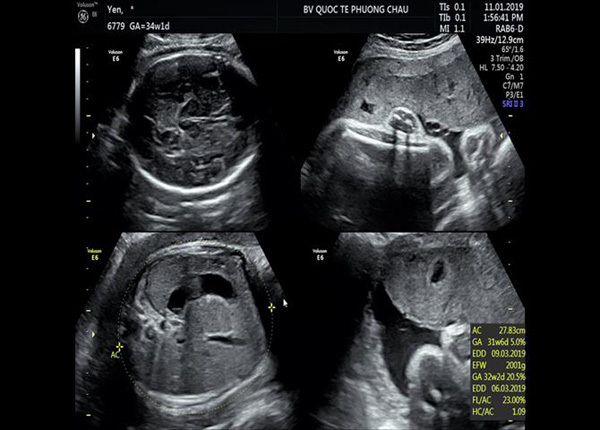

Cuộc phẫu thuật mổ ngang đoạn dưới lấy thai với phương pháp vô cảm gây tê tủy sống, bé trai nặng 2000gr, con sản phụ N.T.H.Y, 29 tuổi đã cất tiếng khóc chào đời vào lúc 19h40 tại BV Phương Châu Sa Đéc.

Sau sinh, bé khóc ngay có phản xạ, trương lực cơ tốt, môi hồng, nhịp tim 140 lần/phút. Mười phút sau đó, bé bắt đầu thở nhanh, nông, co kéo cơ liên sườn, thở rên, phổi kém thông khí, tim đều, bụng mềm. Bé được chẩn đoán là hội chứng suy hô hấp của trẻ sơ sinh/non tháng. Tiếp tục theo dõi do bệnh màng trong, bé được chuyển về sơ sinh thở NCPAP, tiến hành đặt Catheter tĩnh mạch rốn.